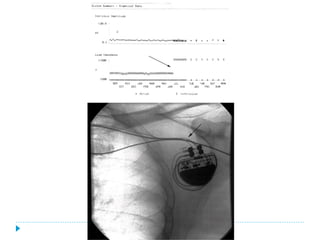

Evaluación del Marcapaso

   Historia clínica, ECG y Rx de tórax.

   Interrogación del MP.

   Al ECG la presencia de espigas de MCP seguidas de capturas 1:1

sugiere un funcionamiento normal.

   Si la FC intrínseca es suficientemente alta para suprimir el MCP

no aparecerán espigas en el ECG. En este caso el acercamiento

de un imán sobre el MCP eliminará la función de sensado y la

frecuencia de las espigas puede ser determinada.